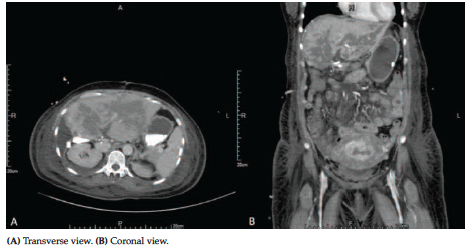

During hospitalization, the patient had persistent hypertension and disturbed vision, with devel-opment of headache. A nonenhanced brain computed tomography showed no intracranial hemorrhage or other significant findings. Therefore, brain magnetic resonance imaging was performed and PRES was diagnosed based on symmetrical lesions in the bilateral occipital lobes (Figure 1). Antihypertensive agents for aggressive blood pressure management and hydrocortisone for improving vasogenic edema were administered. With her hemodynamic con-dition relatively stable, the patient received emergent LDLT.

Four days after transplant, the patient had a seizure attack with loss of consciousness. Repeated brain magnetic resonance imaging scans showed diffuse swelling of cerebrum and cerebellum with uncal herniation and brainstem compression, so PRES progression was highly suspected. With thorough surveys of triggers, besides liver transplant, tacrolimus intoxication (therapeutic drug level of 21.4 ng/mL) was thought to be the primary cause to worsen PRES. Because of this, tacrolimus was promptly suspended. After the abrupt episode, rapid impairment of liver function, hyperbilirubinemia, thrombocytopenia, and prolonged prothrombin time/activated partial thromboplastin time occurred. Doppler sonography showed reduced flow of grafted intrahepatic vessels without thrombotic formation of anastomotic sites (Figure 2). An emergent computed tomography with contrast of abdomen showed hypo- and nonen-hancement (Figure 3), and gross hepatic infarction was diagnosed. The patient gradually deteriorated with sequential multiple organ failure and died 7 days after LDLT.